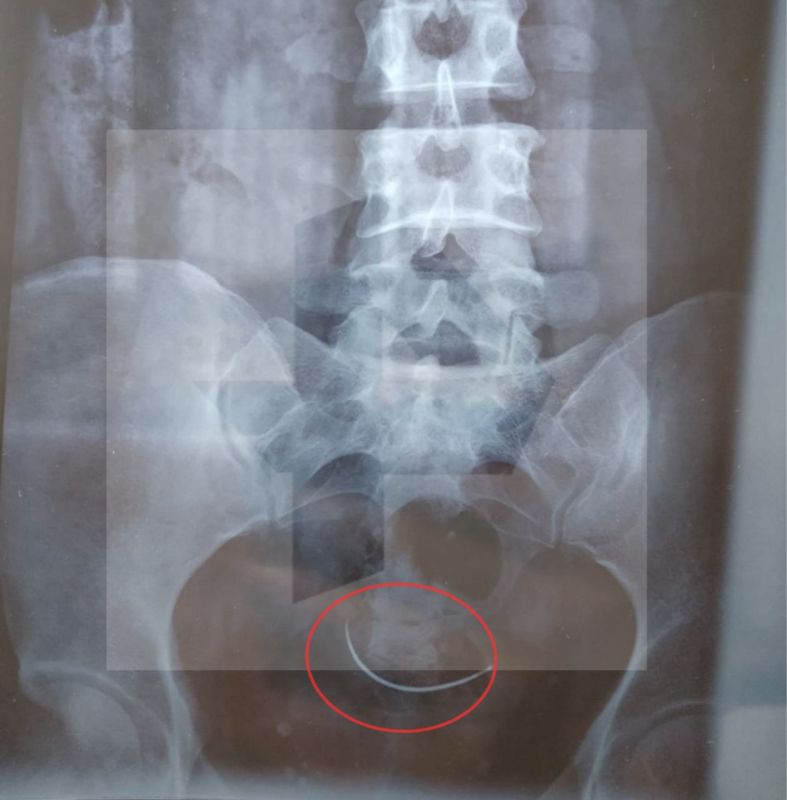

Об этом сообщил источник РЕН ТВ.Пострадавшая даже не догадывалась, что в ее организме есть какой-то инородный предмет, пока три месяца назад не упала и на рентгене не обнаружила, что в ее малом тазу осталась медицинская игла.У женщины было...